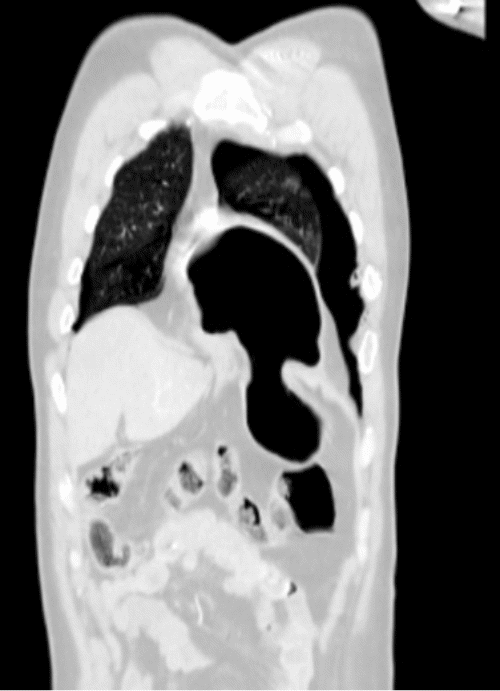

The patient's condition stabilized, and the pain was controlled with analgesia. CT showed no brain injury, but there were multiple left-sided comminuted rib fractures with displacement along the posterior and lateral aspects. In addition, it revealed the presence of hydropneumothorax; lung contusion with thoracic wall subcutaneous emphysema; right-sided mild pneumothorax; undisplaced fracture of the sternal body; herniation of the stomach into the pericardial cavity (Figure 1); no intraabdominal fluid or air and no solid organs injury; fracture of the transverse processes of the L3/L4 and L5 vertebrae; fractures of the left glenoid bone and left pelvic bone; multiple comminuted displaced fractures involving the iliac, acetabular, and pubic bones, with the displacement of the iliac bone fractures; right inferior pubic ramus nondisplaced fractures; and fracture of the left sacral alar and proximal left sacral segments (Figure 2).

Figure 1. CT of Herniated Stomach into Pericardial Space. A) Scout, (B) Axial, (C) Sagittal, and (D) Coronal Views. Published with Permission

B) Axial View

D) Coronal View